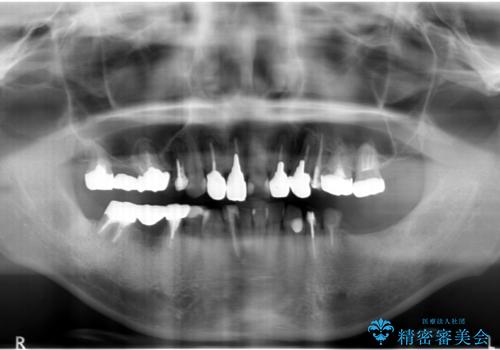

- 「少しずつ色々な箇所が悪くなり、歯医者に通い続けている。全ての歯を長持ちするような状態にできるような治療を受けたい。」、と全顎・総合的な治療を希望され来院されました。

根管治療・矯正治療・歯周外科・セラミック補綴を含む様々な治療オプションを駆使し、長期間良好な状態に保てるような治療計画を立案します。

矯正治療を絡めた総合的な治療をお行なったことで、理想的な咬合関係を確立し安定した噛み合わせで仕上げることができました。

また歯周外科を行うことで歯ぐきの腫れを改善し、清掃性を高めています。